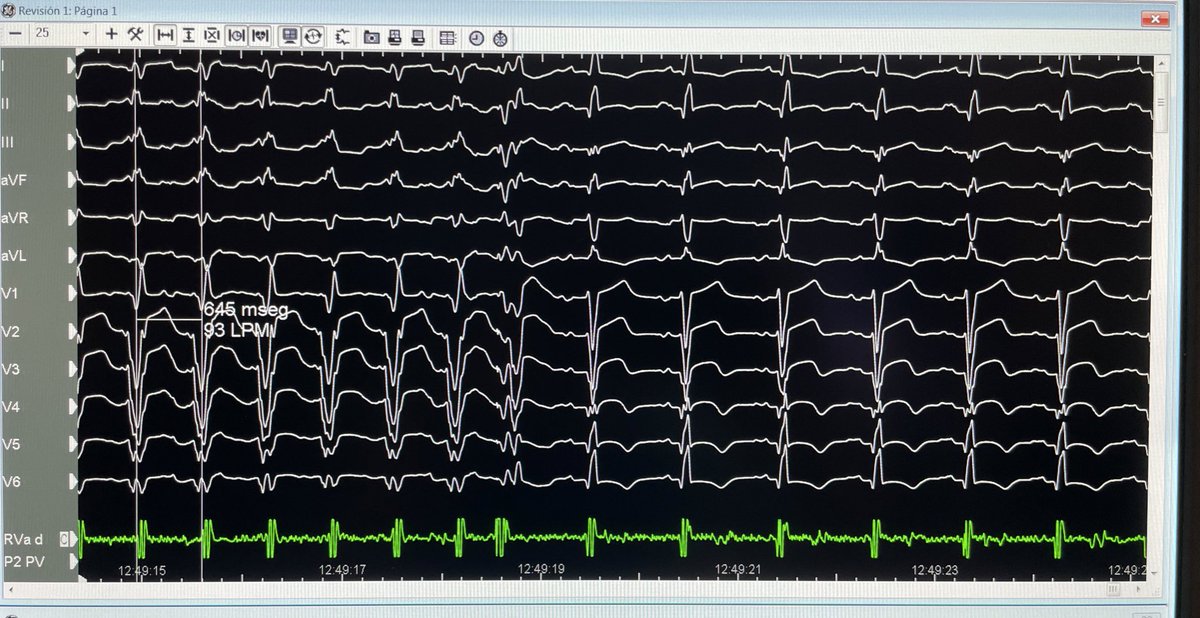

Incessant slow #VT with intramural circuit in end-stage HCM despite previous #VTablations. Coil insertion in a small branch of 2nd diagonal coronary artery. CT integration in the #EPlab❤️ at Miguel Servet University Hospital. #EPeeps @EPeeps_Bot @secardiologia @escardio